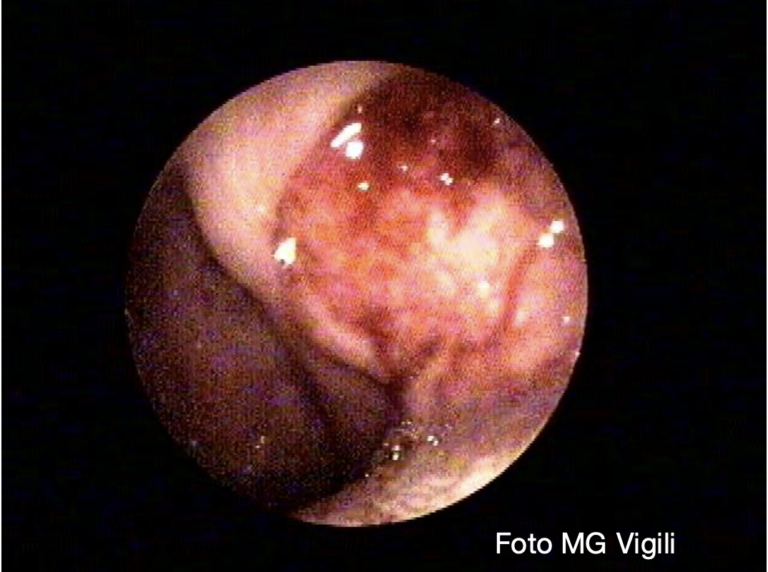

Maggior rischio di metastasi linfonodali nei giovani con carcinoma squamoso della tonsilla T1

Metastasi linfonodali controlaterali nei carcinomi squamosi della tonsilla